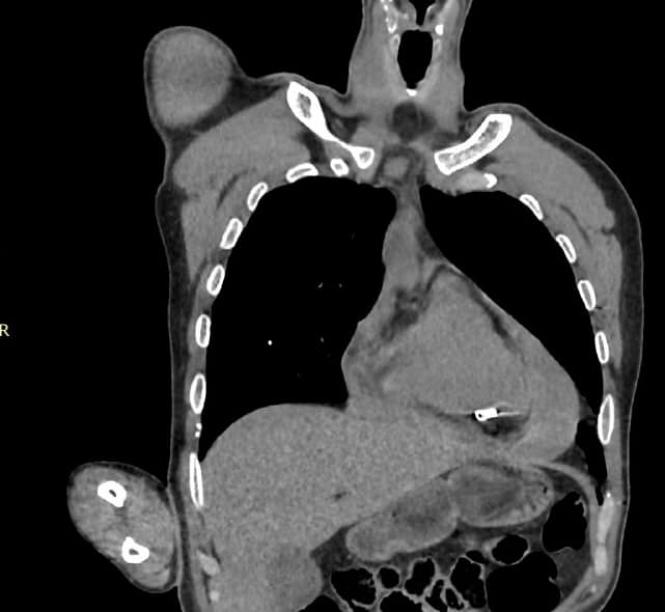

- У прифронтовому госпіталі хірурги Медичних сил Збройних Сил України успішно провели операцію з порятунку життя військовослужбовця, який отримав мінновибухове поранення з ознаками вогнепального поранення серця і тампонадою.

Мінновибухове поранення з ознаками вогнепального поранення серця і тампонадою — важке поранення з загрозою для життя, яке потребувало швидкого оперативного втручання. Ситуацію ускладнювали бойові дії, які точаться неподалік госпіталю. Але наші медики впоралися. Стан пораненого вдалося стабілізувати.